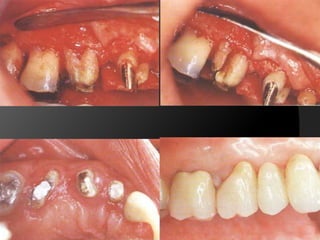

Planificación Del Tratamiento En Restauraciones UnitariasRestauraciones Extracoronarias

Estructura coronaria insuficiente para retener la restauración dentro de la corona del dienteEstructura dentaria defectuosa o socavadaModificar los contornos para mejorar la oclusión o la estética

CORONA DE RECUBRIMIENTO PARCIAL: Corona de deja una o más superficies axiales sin cubrir. Proporciona retención moderada.

CORONA COMPLETA EN METAL: 	En dientes con múltiples superficies axiales defectuosas o destruidas. Proporciona la máxima retención.	La superficie oclusal	favorece  el chequeo oclusal

CORONA COMPLETA METAL-CERÁMICA: Iguales indicaciones que la metálica pero  estética

CORONA TOTALMENTE CERÁMICA: Combinación de recubrimiento completo y máxima estética. La eliminación de estructura dentaria es mayor.

Planificación Del TratamientoEn Restauraciones UnitariasRestauraciones Extracoronarias

Estructura coronaria insuficientepara retener la restauración dentro de la corona del dienteEstructura dentaria defectuosa o socavadaModificar los contornos para mejorar la oclusión o la estética

CORONA DE RECUBRIMIENTOPARCIAL: Corona de deja una o más superficies axiales sin cubrir. Proporciona retención moderada.

CORONA COMPLETA ENMETAL: En dientes con múltiples superficies axiales defectuosas o destruidas. Proporciona la máxima retención. La superficie oclusal favorece el chequeo oclusal

CORONA COMPLETA METAL-CERÁMICA:Iguales indicaciones que la metálica pero estética

CORONA TOTALMENTE CERÁMICA:Combinación de recubrimiento completo y máxima estética. La eliminación de estructura dentaria es mayor.